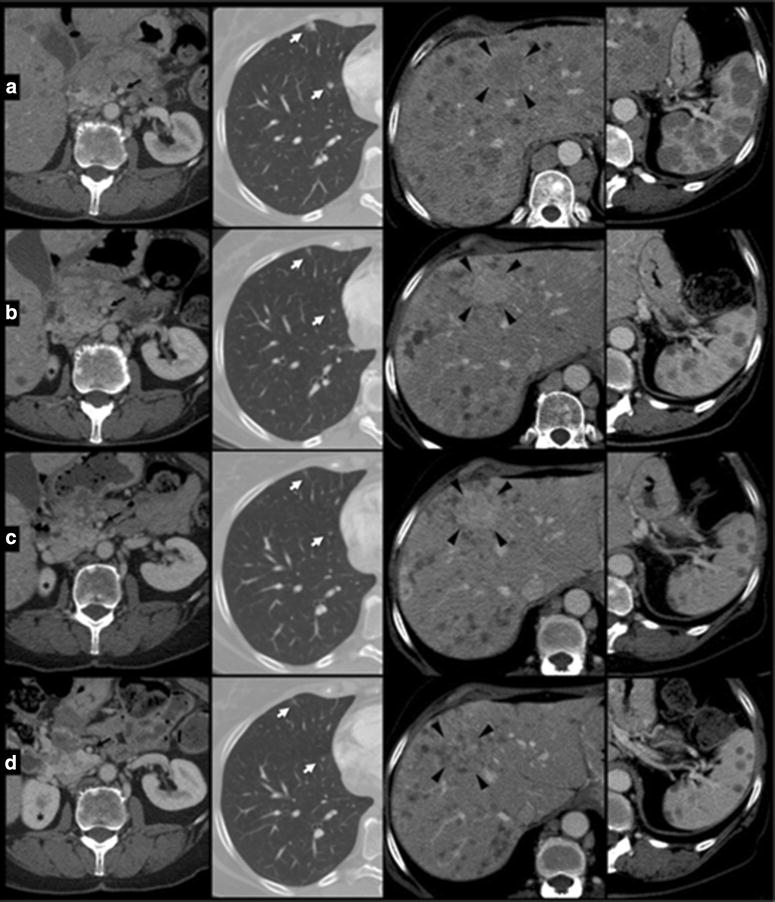

Fig. 6.

Changes of lesions over time in pancreatic head region, lung, liver and spleen at time 0 (a) and at 4 (b), 7 (c), 10 month (d) follow up examinations. Pancreas: enlargement of pancreatic head region was observed at time 0, with strongly inhomogeneous density, indistinct pancreatic margins and surrounding retroperitoneal fat stranding; some peripancreatic lymph nodes enlarged were detected. Following CT examinations show gradually decrease of pancreatic swelling with better definition of parenchymal lesions, going towards progressive regression e colliquation. Note progressive appearance of right kidney’s upper pole asterisk, according to reduction of displacement effect by liver. Furthermore, note the displacement of superior mesenteric artery (black arrow) to right side due to reduction of pancreatic swelling. Lung: progressive volume reduction of metastatic lesions (white arrow) in anterior basal segment of right lower pulmonary lobe. Liver: one of the major lesions of the liver at the IV segment (arrowhead) underwent progressive volume reducing ad enhancement pattern. Spleen: volume reduction of multiple metastatic lesions

On August 2014, the patient had a significant clinical benefit with improvement of performance status (ECOG PS: 0). The total body CT-scan performed on October 2014 evidenced a RECIST partial response (Figs. 4, 5, 6) with reduction in number and volume of liver and spleen metastases, reduction of hepatomegaly and splenomegaly, reduction of periesofageal, retrocrural and lomboaortic lymphnodal metastases, reduction of lung metastases, disappearance of ascites, significantly reduction of the lesion of the pancreatic head.

The patient continued the treatment and the total body CT-scan performed on January 2015 showed once again the persistence of the framework of further instrumental disease response, on lung, liver, and multiple lymphnodal metastases. Then, given the response both clinical and radiological and considering the improvement in quality of life and Performance Status achieved by the patient, we continued the treatment with temozolomide at the same dosage and regimen. In April 2015, the patient, stable for clinical conditions (PS = 0), with very good quality of life, performed a new total body CT-scan (Figs. 4, 5, 6) which showed an unexpected, further partial response. Treatment with TMZ is still ongoing.